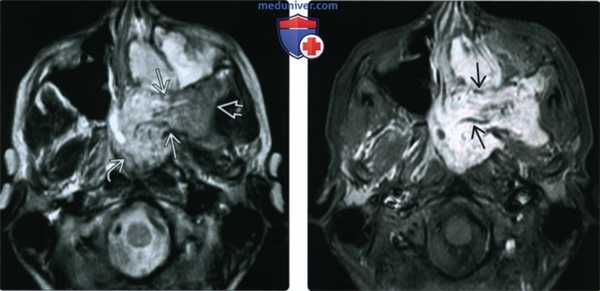

(Слева) При аксиальной МРТ Т2 у юного пациента мужского пола визуализируется большая инфильтративная ЮАФ в типичном месте. Опухоль находится в клиновидно-небном отверстии и распространяется кнаружи в жевательное пространство и кнутри в носоглотку.

(Справа) При аксиальной МРТ Т1 С+ FS у этого же пациента определяется интенсивное контрастирование опухоли. В ней видны несколько извитых участков выпадения сигнала, сопоставимых с расширенными питающими сосудами.